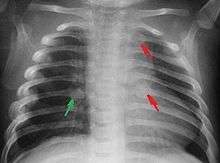

The immediate physical effects of abuse or neglect can be relatively minor (bruises or cuts) or severe (broken bones, hemorrhage, or even death). In some cases the physical effects are temporary; however, the pain and suffering they cause a child should not be discounted. Rib fractures may be seen with physical abuse, and if present may increase suspicion of abuse, but are found in a small minority of children with maltreatment-related injuries.[61][62]

Most nations with child abuse laws deem the deliberate infliction of serious injuries, or actions that place the child at obvious risk of serious injury or death, to be illegal bruises, scratches, burns, broken bones, lacerations, as well as repeated "mishaps," and rough treatment that could cause physical injury, can be physical abuse.[19] Multiple injuries or fractures at different stages of healing can raise suspicion of abuse.